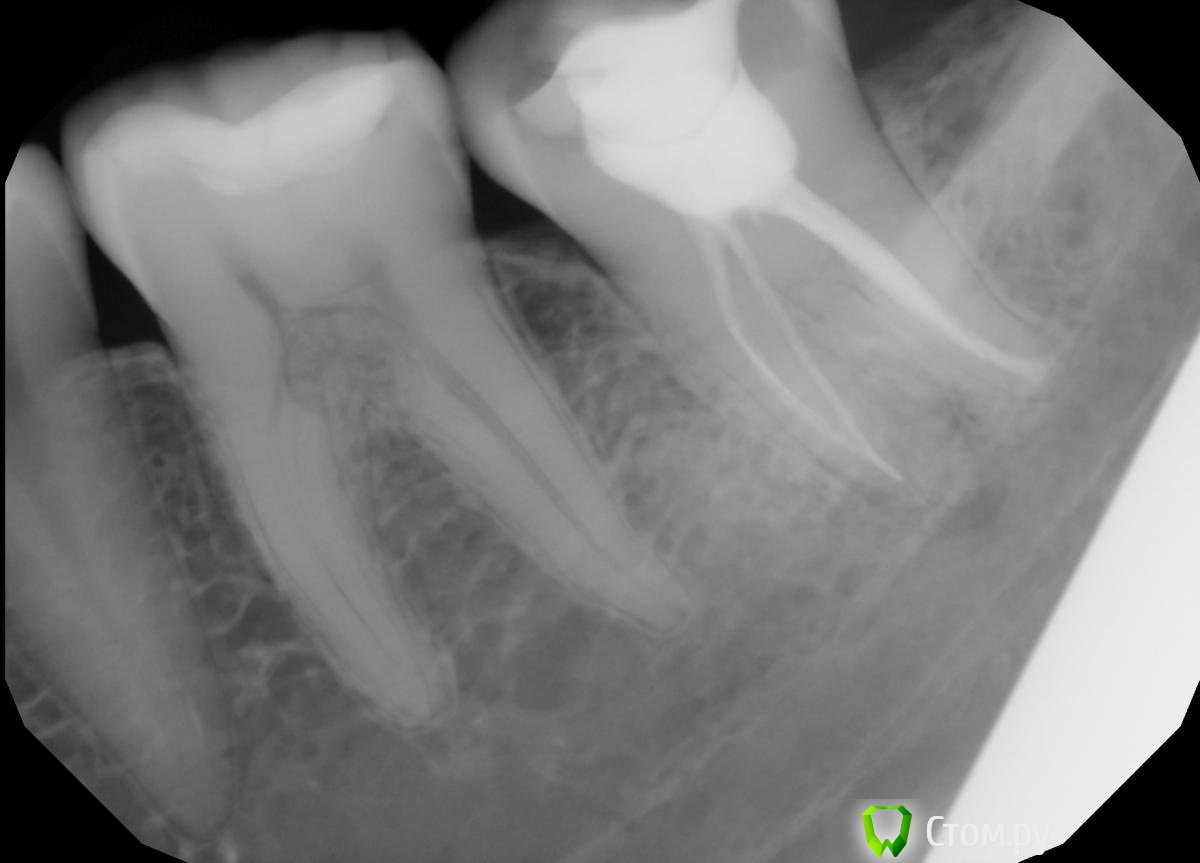

Valerkaa Опубликовано 25 сентября, 2014 Поделиться Опубликовано 25 сентября, 2014 Всем добрый вечер! Родственнице делали снимки 3.7, в кадр еще и 3.6 попал .Сама, к сожалению, во рту посмотреть не могу, она живет в другом городе. Но со слов, жалоб никаких, да и внешне тоже все спокойно. На что это похоже? У меня что-то никаких мыслей кроме внутренней резорбции или чего-то такого нет. Доктор отправляет родственницу на МРТ. У кого какие мысли? Ссылка на комментарий